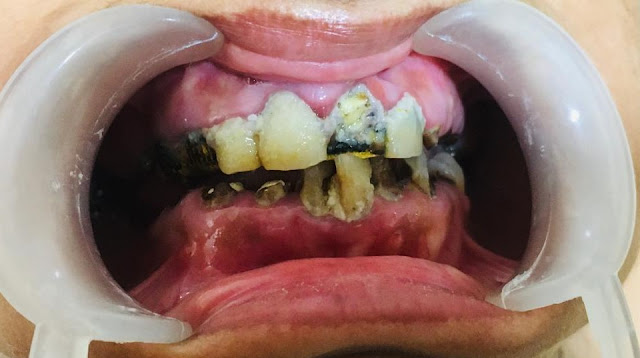

टूथब्रश, टूथपिक या इंटरडेंटल ब्रश का उपयोग से कैलकुलस निकालने योग्य नहीं होता । कैलकुलस को दंत चिकित्सक द्वारा निकालना पड़ता है। दैनिक आधार पर प्लाक को हटाने से कैलकुलस की संभावना कम हो जाती है।